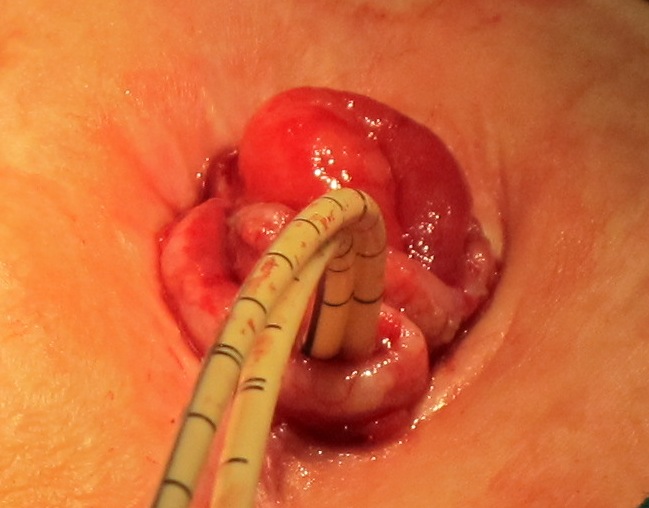

- ФКС : в 12 см от анального жома отверстие свищевого хода оклоо 2см в диаметре с признаками опухолевой инфильтрации.